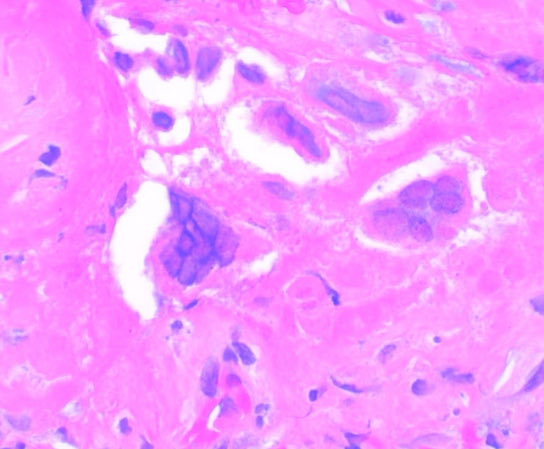

Uterine carcinosarcoma showing serous epithelial carcinoma and liposarcomatous heterologous element 🧐🧐 #Gynecology #WomensHealth #medicine #path #pathology